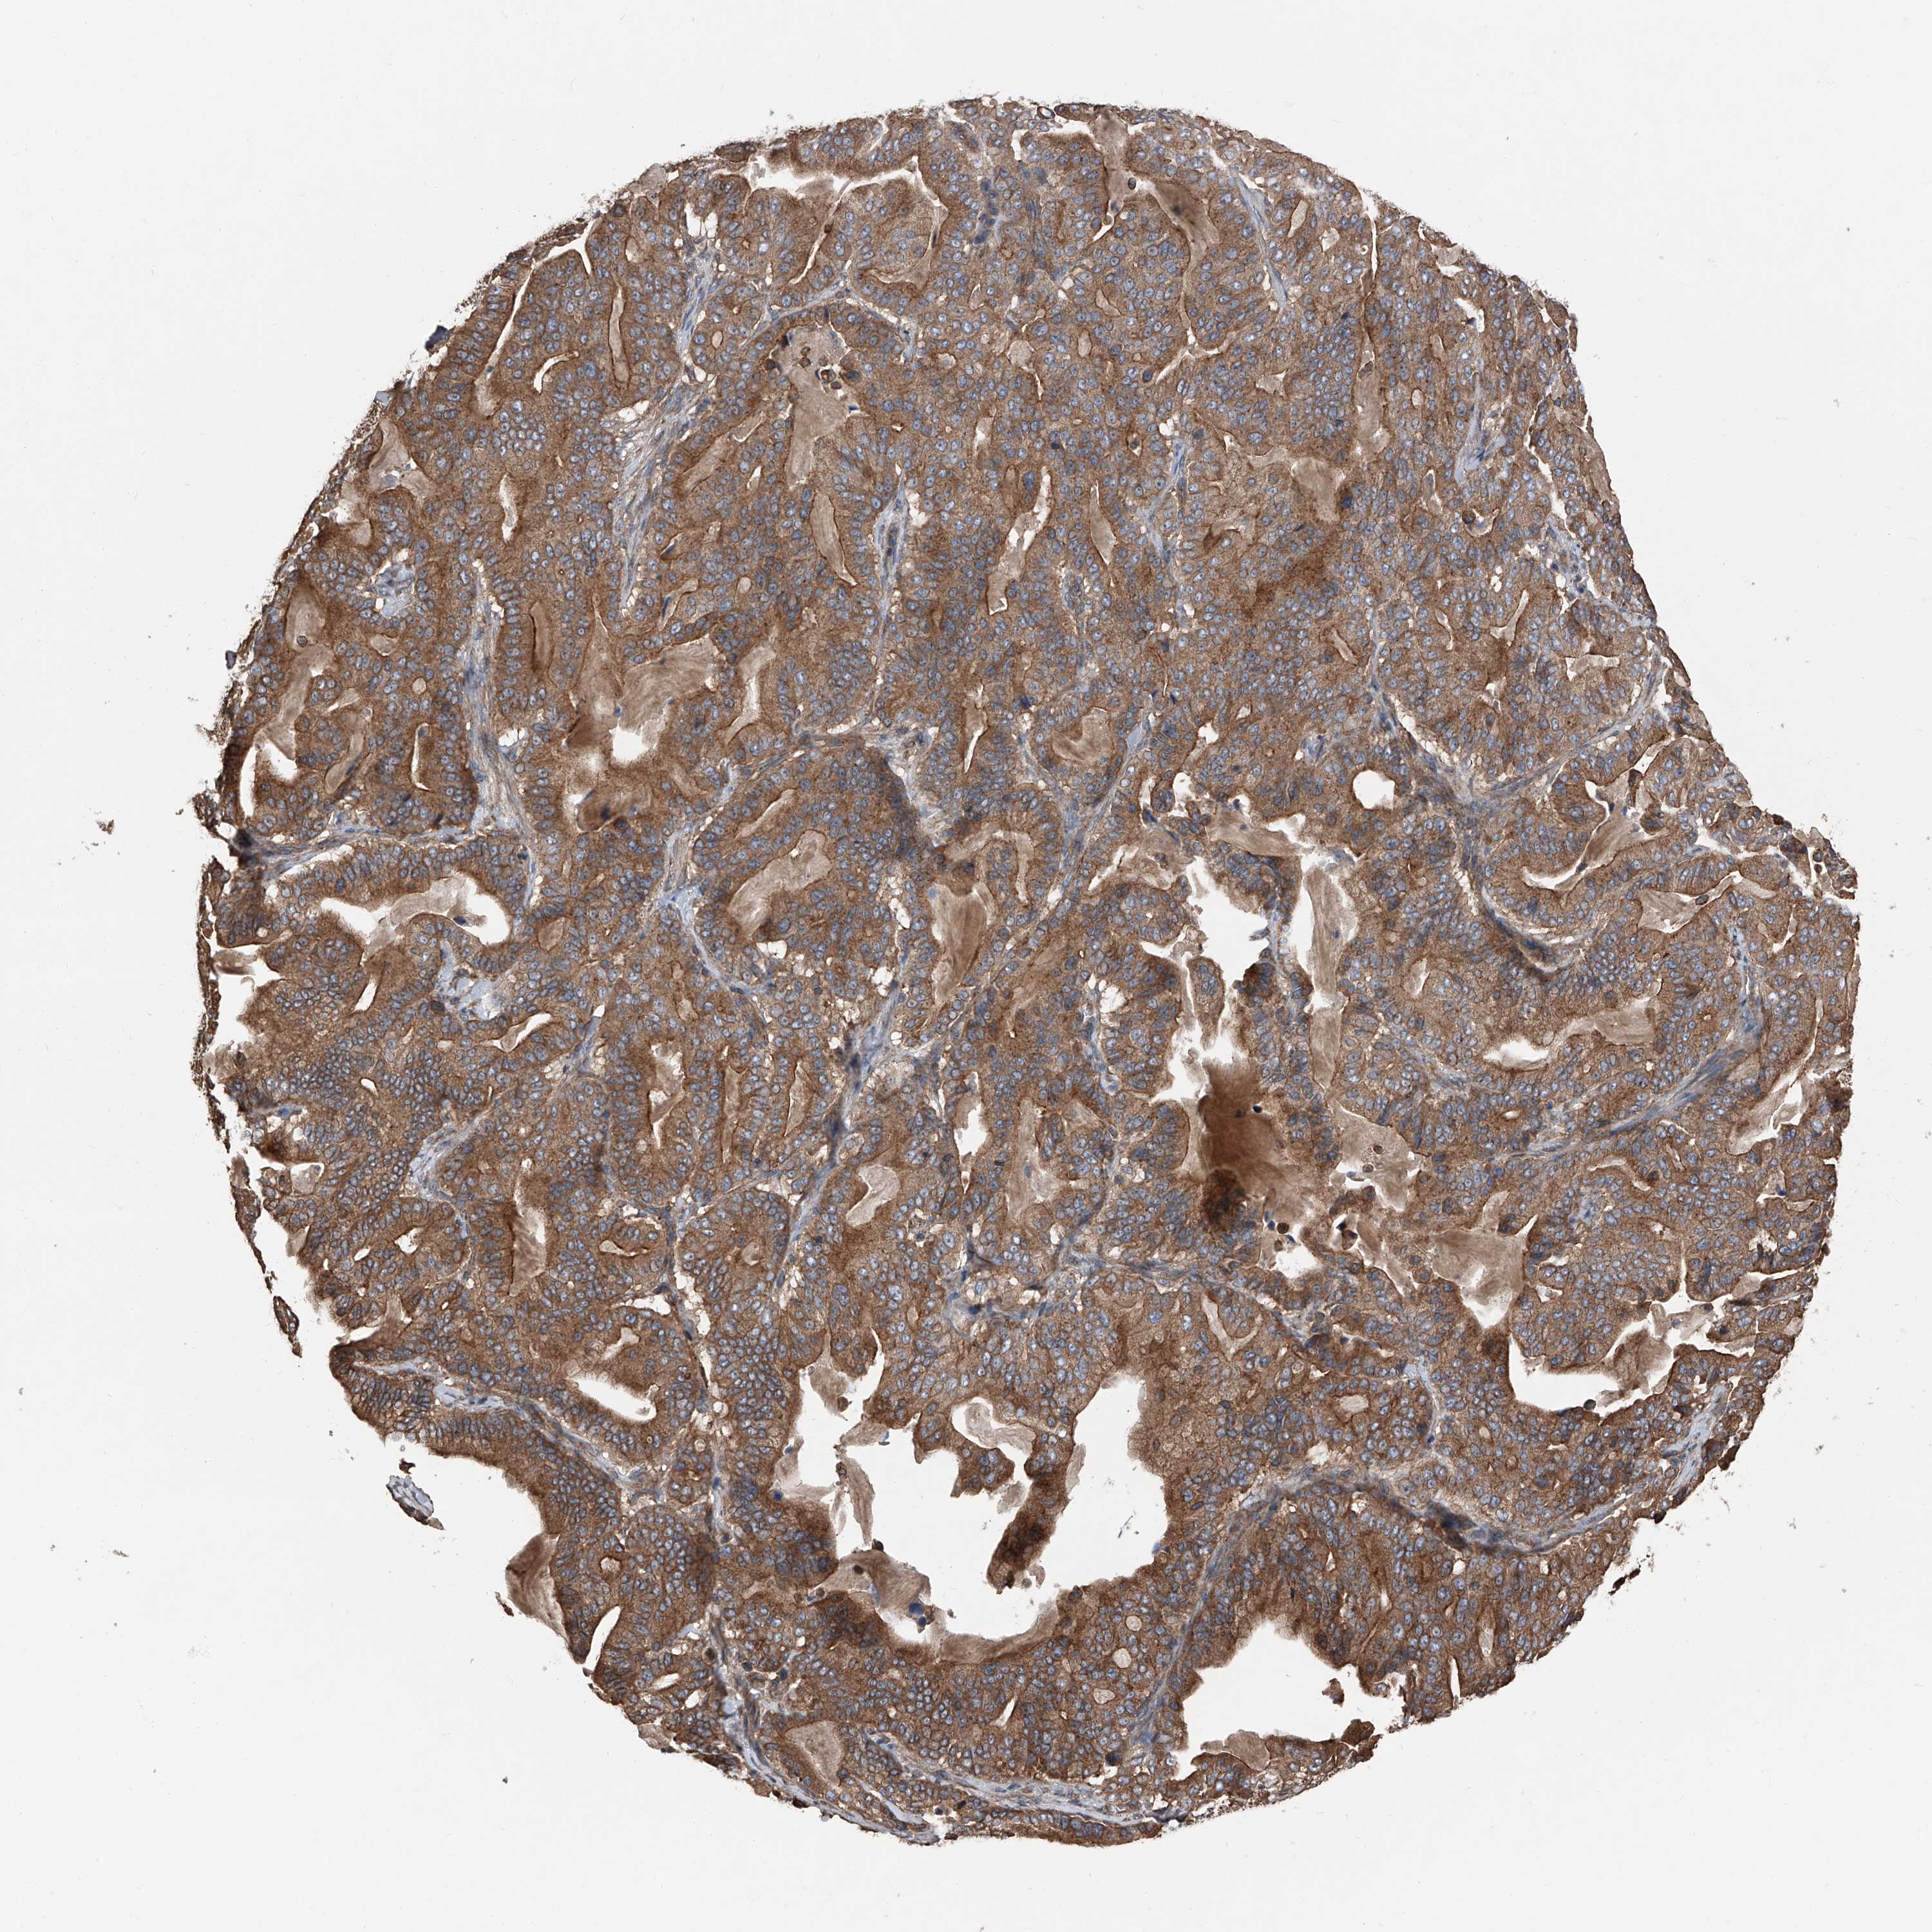

PANCREATIC CANCER - Protein expressioni

A mouse-over function shows sample information and annotation data. Click on an image to view it in a full screen mode. Samples can be filtered based on level of antibody staining by selecting one or several of the following categories: high, medium, low and not detected. The assay and annotation is described here.

Note that samples used for immunohistochemistry by the Human Protein Atlas do not correspond to samples in the TCGA dataset.

Antibody stainingi

Antibody staining in the annotated cell types in the current human tissue is reported as not detected, low, medium, or high, based on conventional immunohistochemistry profiling in selected tissues. This score is based on the combination of the staining intensity and fraction of stained cells.

Each image is clickable and will lead to virtual microscopy that enables deeper exploration of all samples and also displays staining intensity scores, fraction scores and subcellular localization as well as patient and tissue information for each sample.

Antibody HPA029109

Staining

High

Medium

Low

Not detected

Intensity

Strong

Moderate

Weak

Negative

Quantity

>75%

75%-25%

<25%

None

Location

Nuclear

Cytoplasmic/membranous

Cytoplasmic/membranous,nuclear

Adenocarcinoma, NOS